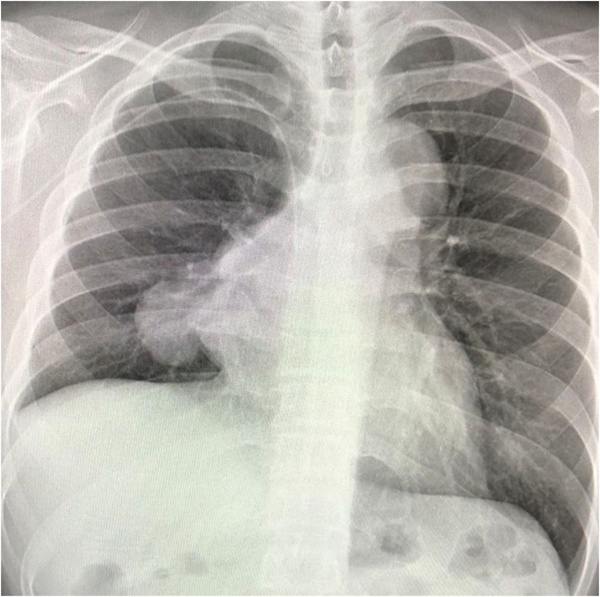

魏先生的胸部X光片顯示肺部陰影

起初魏先生只是反覆發燒和咳嗽,前往社區診所檢查以為只是普通感冒,直到2個月後,依舊反覆不見好轉,檢查血氧後發現遠遠低于正常值範圍,於是在醫生建議下趕緊前往大醫院拍胸片。「看到肺部發白的胸片結果,當時以為是肺炎或者肺結核,後面經過驗血、CT一系列檢查,才被確診為得了血液腫瘤疾病,心情一下好失落。」魏先生回憶。